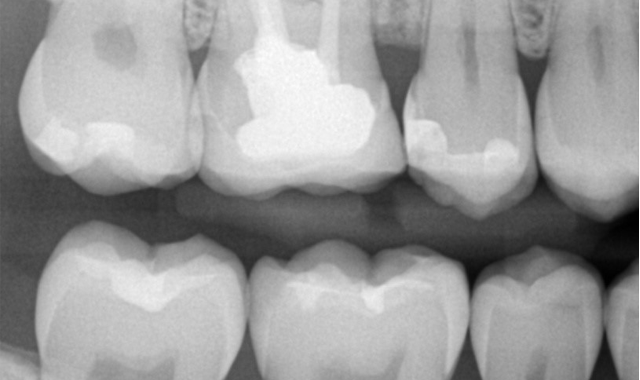

A dental case study showing techniques for treating a proximal caries lesion.

The patient, a 34-year-old white male is in good overall health. He attends routine six-month recall visits for dental prophylaxis but admits he isn’t a regular user of dental floss. He presented with an incipient lesion on the distal of tooth #5. Being an excellent candidate for resin infiltration, the patient opted for this treatment after a brief explanatory discussion.